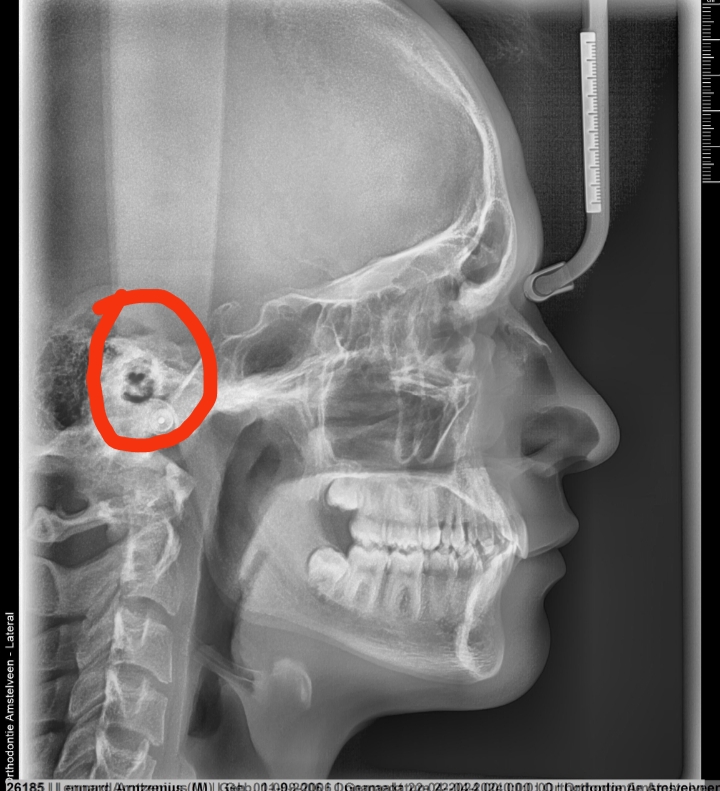

really low iq post but what the fuck is that teeth in which whenever i see x-ray photos is always hidden? i can also feel a teeth on the same spot

Calling this post low iq while not knowing what wisdom teeth arereally low iq post but what the fuck is that teeth in which whenever i see x-ray photos is always hidden? i can also feel a teeth on the same spot

Isn’t this better cause you can literally see the bones?a normal side profile would be easier didnt have to go to these lengths bro